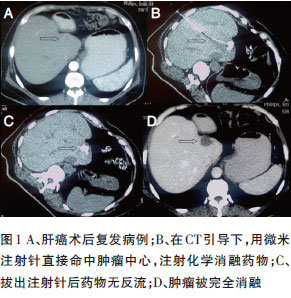

套管针微米注射技术 在CT穿刺引导架引导下,先将直径为0.8 mm的注射针穿刺到肿瘤边缘,将其作为套管针,插入微米注射针(直径为0.45 mm),并将其穿刺入肿瘤内。微米注射针可弯曲,从而可改变穿刺方向,多点注射化学消融药物(图1),且其损伤小,出针时药物反流少,提高治疗效率的同时减少了不良反应。

对于不适合手术及局部物理消融治疗的患者,主要选择化学消融治疗。对于肿块较大者,采用经导管肝动脉化疗栓塞(TACE)与化学消融相结合的“双介入”治疗:对于富血供肿瘤,先行TACE,将肿瘤血管栓塞后,对残留病灶追加化学消融治疗,可使病变达到完全坏死;对于乏血供肿瘤,先行化学消融治疗,将肿瘤的绝大部分消融,再进行栓塞化疗,这样更易发挥疗效。化学消融也可治疗转移性肝癌,特别对于单发肿瘤,可取得良好疗效(图4)。